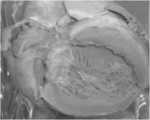

FIG. 7 is a graph of a hypertrophic cardiac sample processed by the method for optimized preservation of gross pathological samples in example 2 of the present invention.

The cardiac hypertrophy specimen is soaked in 10% formalin fixing solution for a long time, the color of the specimen is dull as shown in figure 6, and after the treatment of the invention, the color of the specimen is restored to be close to that of a fresh specimen as shown in figure 7.

Example 3